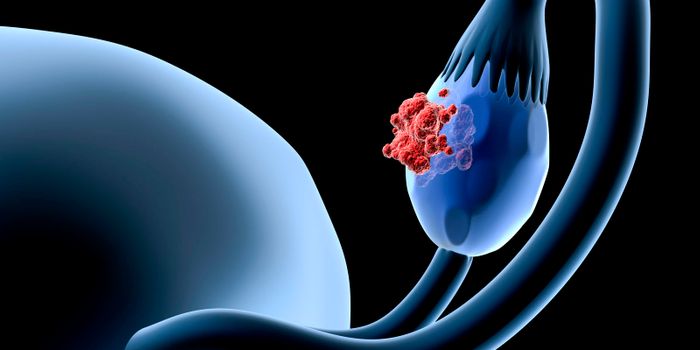

AUG 01, 2016ImmunologyA new treatment for the selective targeting of ovarian cancer cells has been adopted from chimeric antigen receptor (CAR ...

FEB 11, 2022Plants & AnimalsProstate cancer affects about one in eight men each year, and is one of the most common types of cancer in men). Researc ...

MAR 13, 2025CancerA recent study published in JAMA Oncology presents promising new data on a treatment regimen beneficial to patients with ...

OCT 29, 2018ImmunologyTumor cells in breast cancer have proven to evade the immune responses utilizing actin cytoskeleton

APR 24, 2023Clinical & Molecular DXWhen triple-negative breast cancer patients took several prescriptions worth of antibiotics in the three years after the ...

MAY 09, 2023ImmunologyCancer immunotherapy constantly evolves, and discoveries and treatments targeting more aggressive cancers are published ...

OCT 06, 2025CancerLymph nodes, hundreds of small structures located throughout the body, play a pivotal role in immunity, including anti-t ...